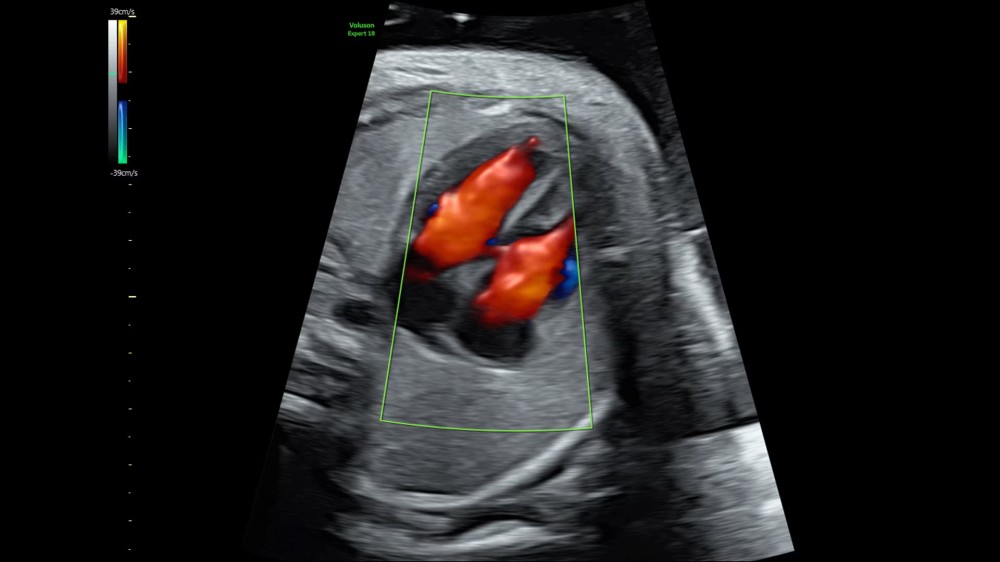

Volumetrik və Doppler Görüntüləmə: Mürəkkəb anatomik strukturların vizualizasiyasını yaxşılaşdırır və dəqiq diaqnostika üçün imkan yaradır.

Görüntüləmə Modları: 2D, 3D/4D, Rəngli Doppler, Power Doppler

Rəngli Doppler, inkişaf etmiş volumetrik görüntüləmə və SonoPelvicFloor funksiyaları cihazın erkən fetal və pelvik patologiyaların aşkarlanması, müdaxilələrin planlaşdırılması və klinik qərarların verilməsi üçün yüksək detal və dəqiqlik təmin etməsinə imkan verir. Bu xüsusiyyətlər Voluson Expert 18-i qadın sağlamlığı sahəsində hərtərəfli və etibarlı ultrasəs diaqnostikası üçün optimal alətə çevirir.